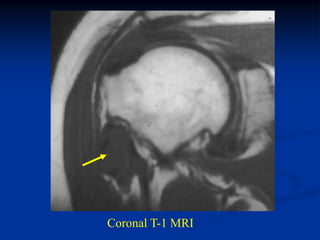

Bone scan

Coronal T-1 MRI

tumor